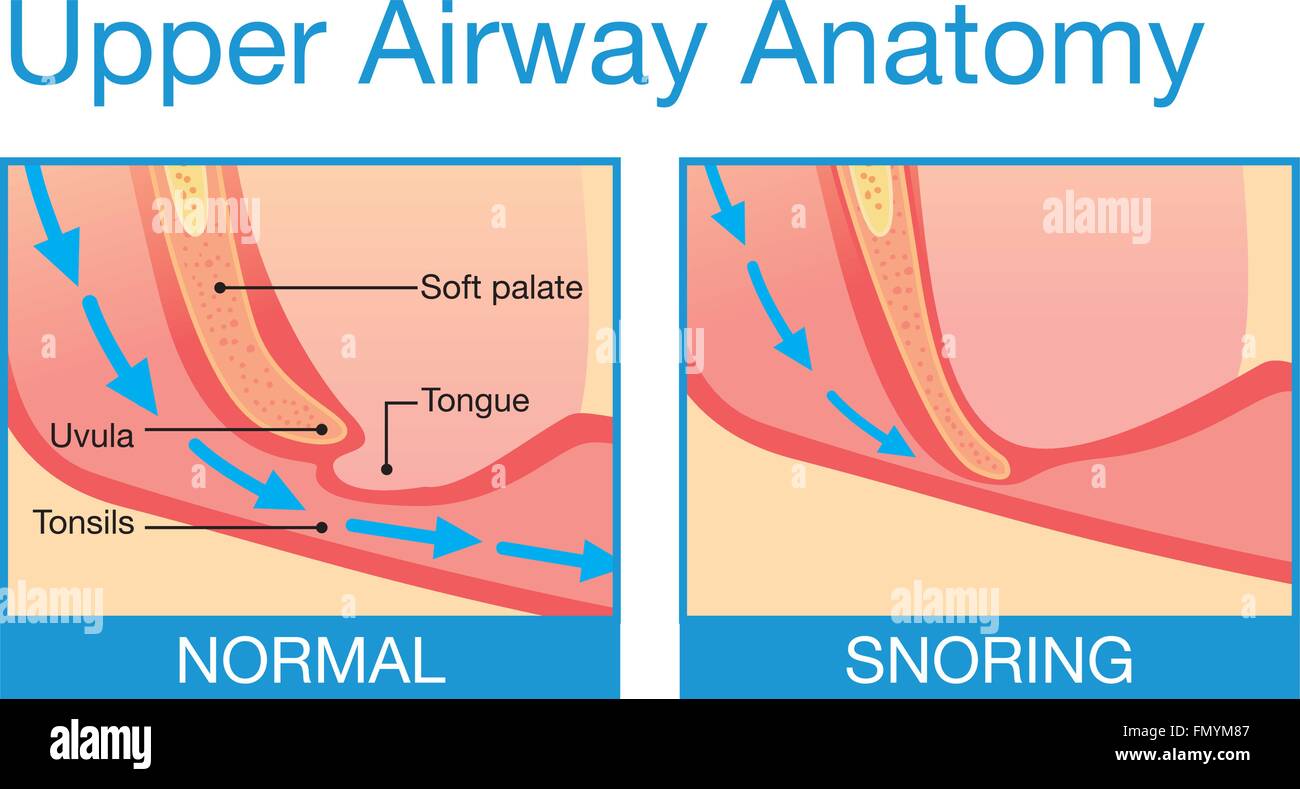

Upper airway human anatomy in normal sleeping and have snoring. Stock Vectorhttps://www.alamy.com/image-license-details/?v=1https://www.alamy.com/stock-photo-upper-airway-human-anatomy-in-normal-sleeping-and-have-snoring-98953575.html

Upper airway human anatomy in normal sleeping and have snoring. Stock Vectorhttps://www.alamy.com/image-license-details/?v=1https://www.alamy.com/stock-photo-upper-airway-human-anatomy-in-normal-sleeping-and-have-snoring-98953575.htmlRFFMYM87–Upper airway human anatomy in normal sleeping and have snoring.